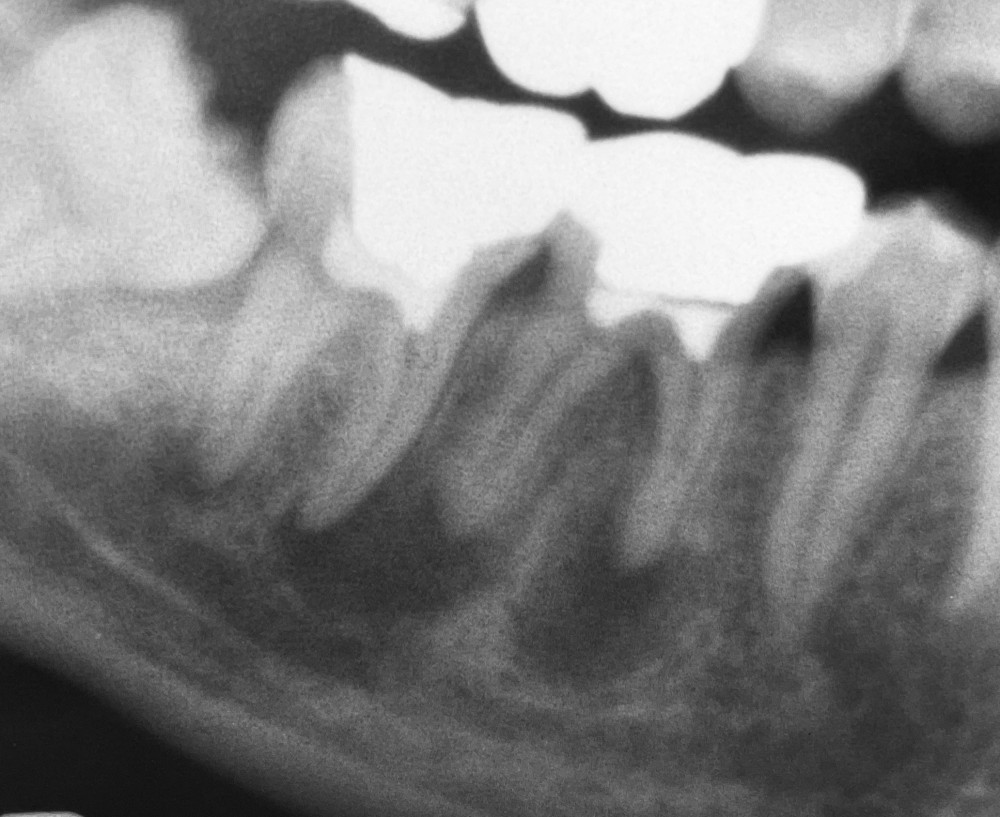

上のエックス線写真は、20代男性、初診時(令和4年12月)のものです。

右下奥歯の痛みを訴え、来院されました。

前医では、おそらく生活歯髄切断という治療を行ったものと推測されます。